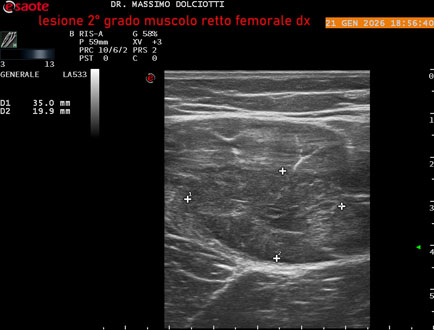

Data inserimento: 23/01/2026

Ecografia del: 21/01/2025

Strumento: Esaote MyLab Eight

Sonda: Lineare Multifrequenza 3-13 MHz

Età Paziente: M 23 anni

Motivazione dell'esame: dolore al terzo prossimale della coscia destra da tre giornii.

Commento all'esame: le immagini ed il video documentano, al terzo prossimale del muscolo retto femorale destro, area disomogenea, ipoecogena, delle dimensioni di 35 mm per uno spessore di 18 mm, misura ottenuta per asse corto o trasversale, e di 71 mm x 20 mm, misura ottenuta per asse lungo o longitudinale, da ricondurre a lesione muscolare di 2° grado con modica raccolta sieroematica intramuscolare.

Conclusioni: lesione di 2° grado del muscolo retto femorale destro (2nd degree injury of the right rectus femoris muscle).